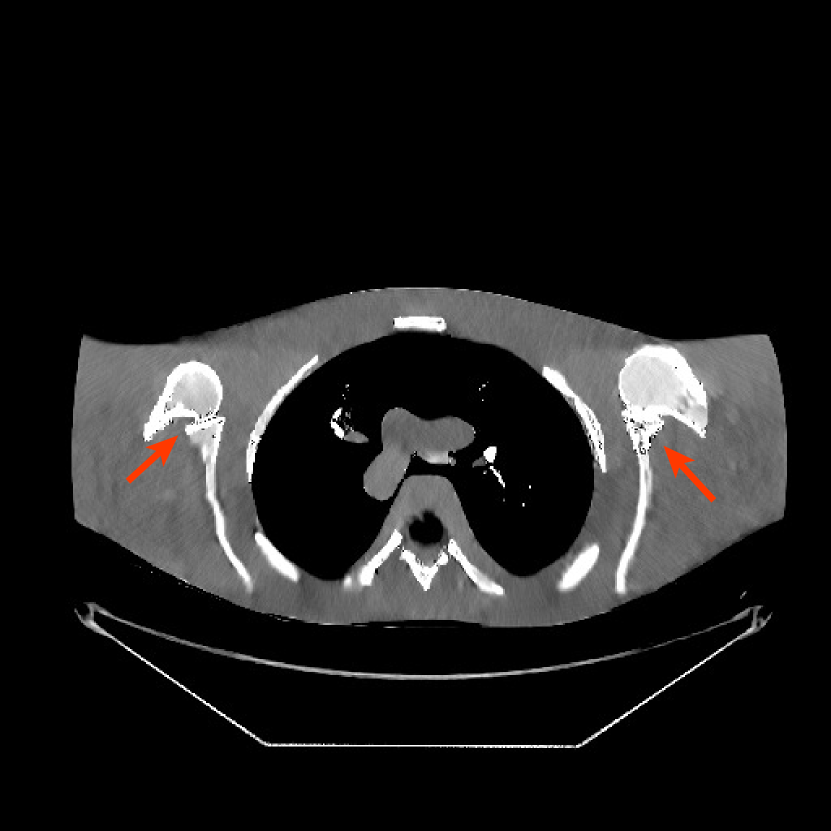

Fig. 9 shows three axial slices from the 3D reconstructions with SPULTRA and PWLS-ULTRA at : the middle slice (No. 67) and two slices located farther away from the center (No. 90 and No. 120). The image profiles along a horizontal line (shown in green) in the displayed slices are also shown in Fig. 9. The reconstructed slices using PWLS-ULTRA appear darker around the center compared to the “true” clinical image and the reconstructions with SPULTRA. This means PWLS-ULTRA produces a strong bias in the reconstruction. The bias can be observed more clearly in the profile plots: the pixel intensities for the SPULTRA reconstruction better follow those of the “true” clinical image, while those for the PWLS-ULTRA reconstruction are much worse than the “true” values. Moreover, SPULTRA achieves sharper rising and failing edges compared to PWLS-ULTRA. In other words, SPULTRA also achieves better resolution than PWLS-ULTRA. Fig. 9 also shows a zoomed-in ROI for each of the chosen slices, and highlights some small details with arrows. It is clear that in addition to reducing the bias, SPULTRA reconstructs image details better than PWLS-ULTRA.